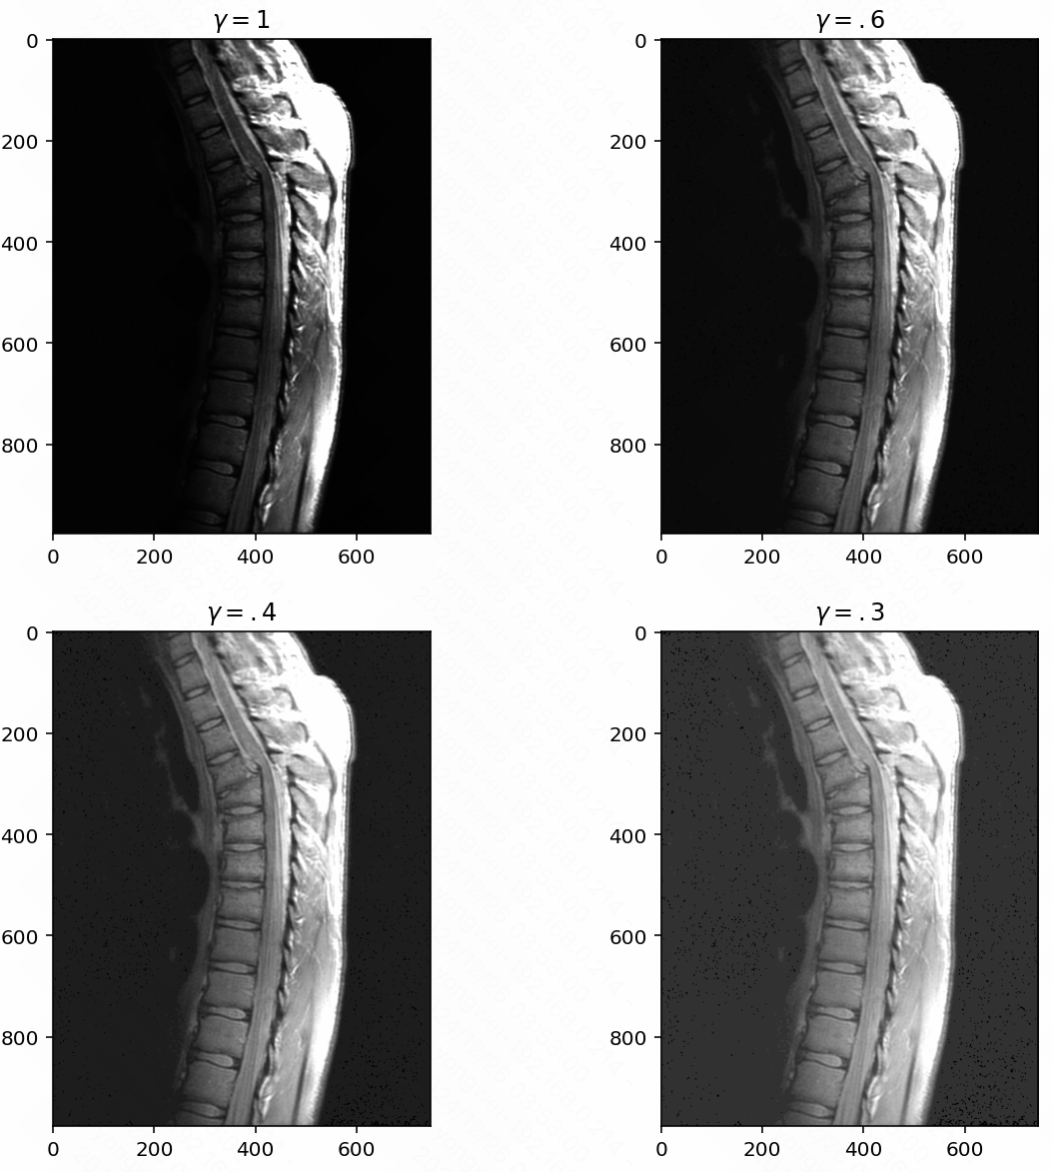

Gamma (Power-Law) Transformation: Corrects non-linear intensity variations, often used in display systems.

3image6 = image**.6

image4 = image**.4

image3 = image**.3